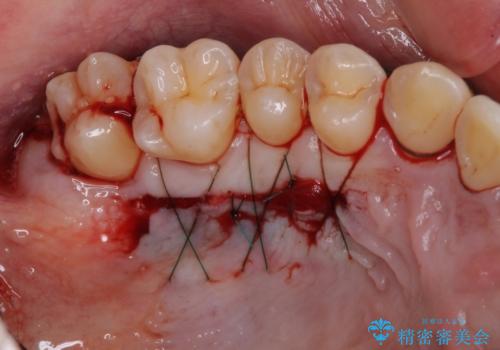

八重歯の歯根が見えている点も気になっているので、矯正歯科治療後に歯肉移植による根面被覆を行うこととしました。

矯正治療により元々気になっていた八重歯と、反対咬合が改善された歯の2本に対して根面被覆を行い、審美面の改善も達成しました。

- 外科手術のため、術後に痛みや腫れ、違和感を伴います